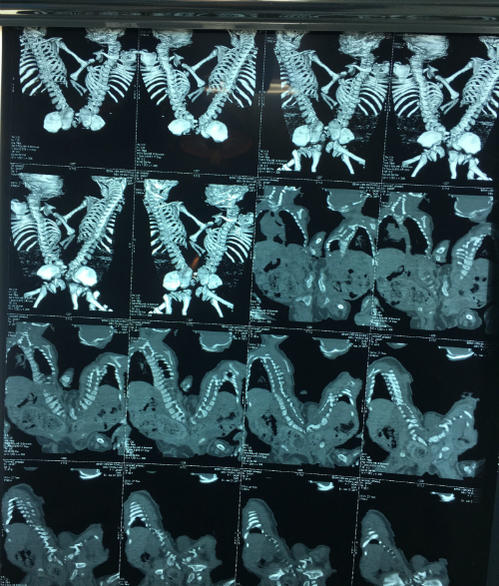

Cặp song sinh chào đời dính nhau phức tạp vùng cùng cụt, được bác sĩ Bệnh viện Nhi đồng 2 mổ tách thành công ngày 23/8.

Hai bé gái Bảo Ân, Bảo Hân nhập viện tháng 8/2016, trải qua ba lần phẫu thuật đặt túi giãn da, một lần mổ cắt lọc lấy túi giãn da ra và khâu lại. Sau quá trình điều trị kéo dài một năm, các bác sĩ đã hội chẩn, thực hiện các xét nghiệm, kiểm tra và quyết định phẫu thuật tách dính.

Ảnh: Hai bé song sinh dính nhau vùng cùng cụt

Tình trạng dính nhau của hai cháu bé trước mổ. Ảnh: B.V

Bác sĩ Phạm Ngọc Thạch, Phó Giám đốc Bệnh viện Nhi đồng 2 cho biết kíp mổ với nhiều y bác sĩ các chuyên khoa đã cùng trải qua 11 giờ phẫu tách cho cặp song sinh. Các phẫu thuật viên đã rạch da bóc tách các lớp vào đến túi thoát vị, rồi mở màng cứng và tách tủy. Sau đó kíp mổ tách phần dính xương cùng và trực tràng tầng sinh môn, hoàn thành việc tách rời và khâu che màng cứng, che phủ vạt da, làm hậu môn tạm kiểu hai đầu rời.

Dự đoán trước phẫu thuật các cháu bị thoát vị màng tủy, khi phẫu tích xác định tình trạng thoát vị tủy - màng tủy nên ca mổ đối diện nhiều khó khăn. Cuộc phẫu thuật diễn ra từ 7h sáng và kết thúc thành công lúc 18h35 ngày 23/8. Hai cháu bé hiện được theo dõi sát trong phòng hồi sức, tình trạng lâm sàng tạm ổn, còn thở máy, kháng sinh, dịch truyền.